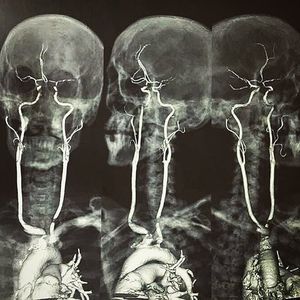

Here is an contrasted CT angiography showing the origin, length & circulation of the carotid arteries!! By having a quick look, these are actually very diseased vessels. There's a lot of stenosis at the origin of the right brachiocephalic and left common carotid. There's also intermittent narrowing of the intracranial vessels, indicating atherosclerosis. The carotid artery begins at the aorta in the chest as the common carotid and courses up through the neck to the head. Place your hands on either side of your neck, and you can feel your pulse in your carotid arteries. Near the larynx, the common carotid divides into the external and internal carotid arteries. The external carotid arteries supply blood to the face and scalp. The internal carotid arteries supply blood to the brain. The most common location of atherosclerotic plaque buildup is the carotid bifurcation, where the common carotid divides into the internal and external carotid arteries.